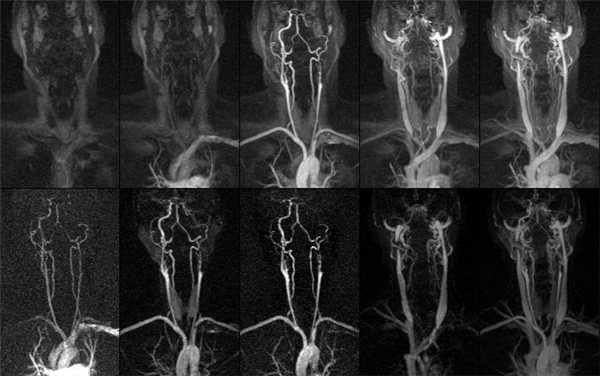

3D-реконструкция артерий шеи при КТА

КТ-ангиография сосудов шеи визуализирует артерии и вены брахиоцефального бассейна. С помощью специальной компьютерной программы, позволяющей придать изображениям объем, рентгенолог видит притоки и мелкие коллатерали, внутренние причины нарушения кровотока, патологические процессы в близлежащих тканях и органах, оказывающие компрессионное действие на артерии и вены. Что показывает КТ сосудов шеи:

На томограммах четко прослеживается архитектоника сосудов исследуемой области

КТ-ангиография сосудов шеи с контрастом незаменима при травмах: скорость получения результата и отличная визуализация сосудистых катастроф, повреждений костных структур и нервных тканей позволяют быстро определить тактику ведения пациента. Большинство патологических процессов протекают генерализованно (атеросклероз, аутоиммунные заболевания), поэтому необходимо исследовать одновременно сосуды головы и шеи на предмет характера поражения и степени выраженности заболевания. На томограммах можно увидеть: